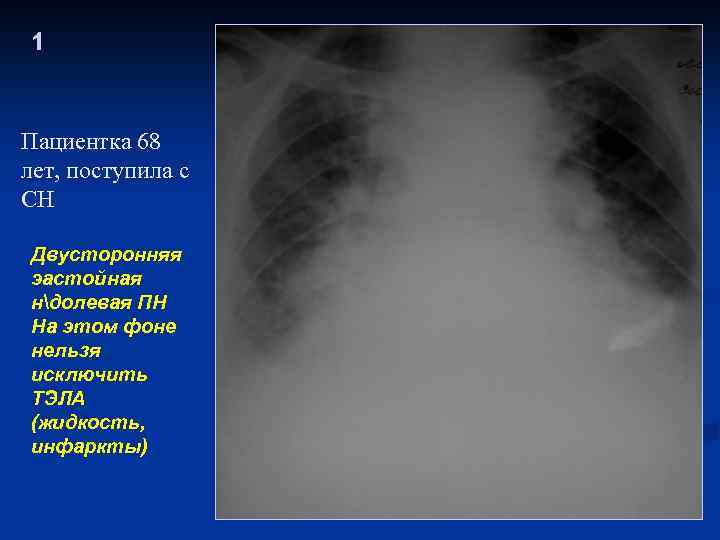

1 Пациентка 68 лет, поступила с СН Двусторонняя эастойная ндолевая ПН На этом фоне нельзя исключить ТЭЛА (жидкость, инфаркты)